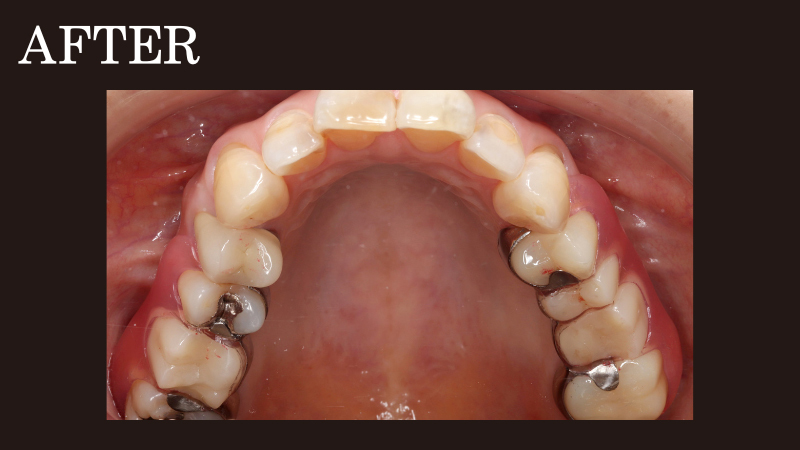

部分入れ歯の症例(10)

ノンクラスプデンチャー

(コンティース)

case10

違和感がなく、しゃべりやすい入れ歯がほしい

50代女性

お口に入れている時の違和感がなく、会話の邪魔にならない入れ歯を希望されて部分入れ歯を作り直した患者さまです。

ご要望を叶えるため、抜歯後に目立たない部分入れ歯「エステショット(ノンクラスプデンチャー)」をお作りしたところ、自然な見た目で入れ歯と気づかれない点やしっかり噛める点は大変ご満足いただきましたが、会話する際の違和感が気になるとお悩みのご様子でした。

そこで新たにご提案したのが、2024年11月に登場した最新の入れ歯「コンティース(ノンクラスプデンチャー)」への作り替えです。

コンティ―スとは、3Dレーザープリンターによるチタン加工技術を用いて開発された新しい入れ歯のこと。

金属が目立ちにくい入れ歯

入れ歯には金属が一部使用されていますが、目立たない位置にあり、入れ歯であることが周囲の人に気づかれにくい設計です。また、この金属部分が滑らかに加工されており、同じノンクラスプデンチャーや他の入れ歯に比べて装着時の違和感が少なくなるよう仕上げられます。

出来上がった入れ歯を患者さまに装着いただいたところ、「入れ歯特有の違和感がなく付け心地がいい」「以前の入れ歯とは比べ物にならないほど話しやすい」と大変喜んでいただけました。

さらに自分の歯で噛んでいた時とほとんど変わらないほど咀嚼力が回復し、しっかり噛めるようになったとの嬉しいお声も。

このように、コンティ―スは発音や会話の邪魔にならない入れ歯です。加えてお口を開けても入れ歯と気づかれにくいため、周囲の目線を気にせず思いきり笑ったり、会話を楽しんだりできます。

コンティース(ノンクラスプデンチャー)で治療。

右上:220,000円

左上:220,000円

計:440,000円(税込)

治療期間・回数

3週間・2回